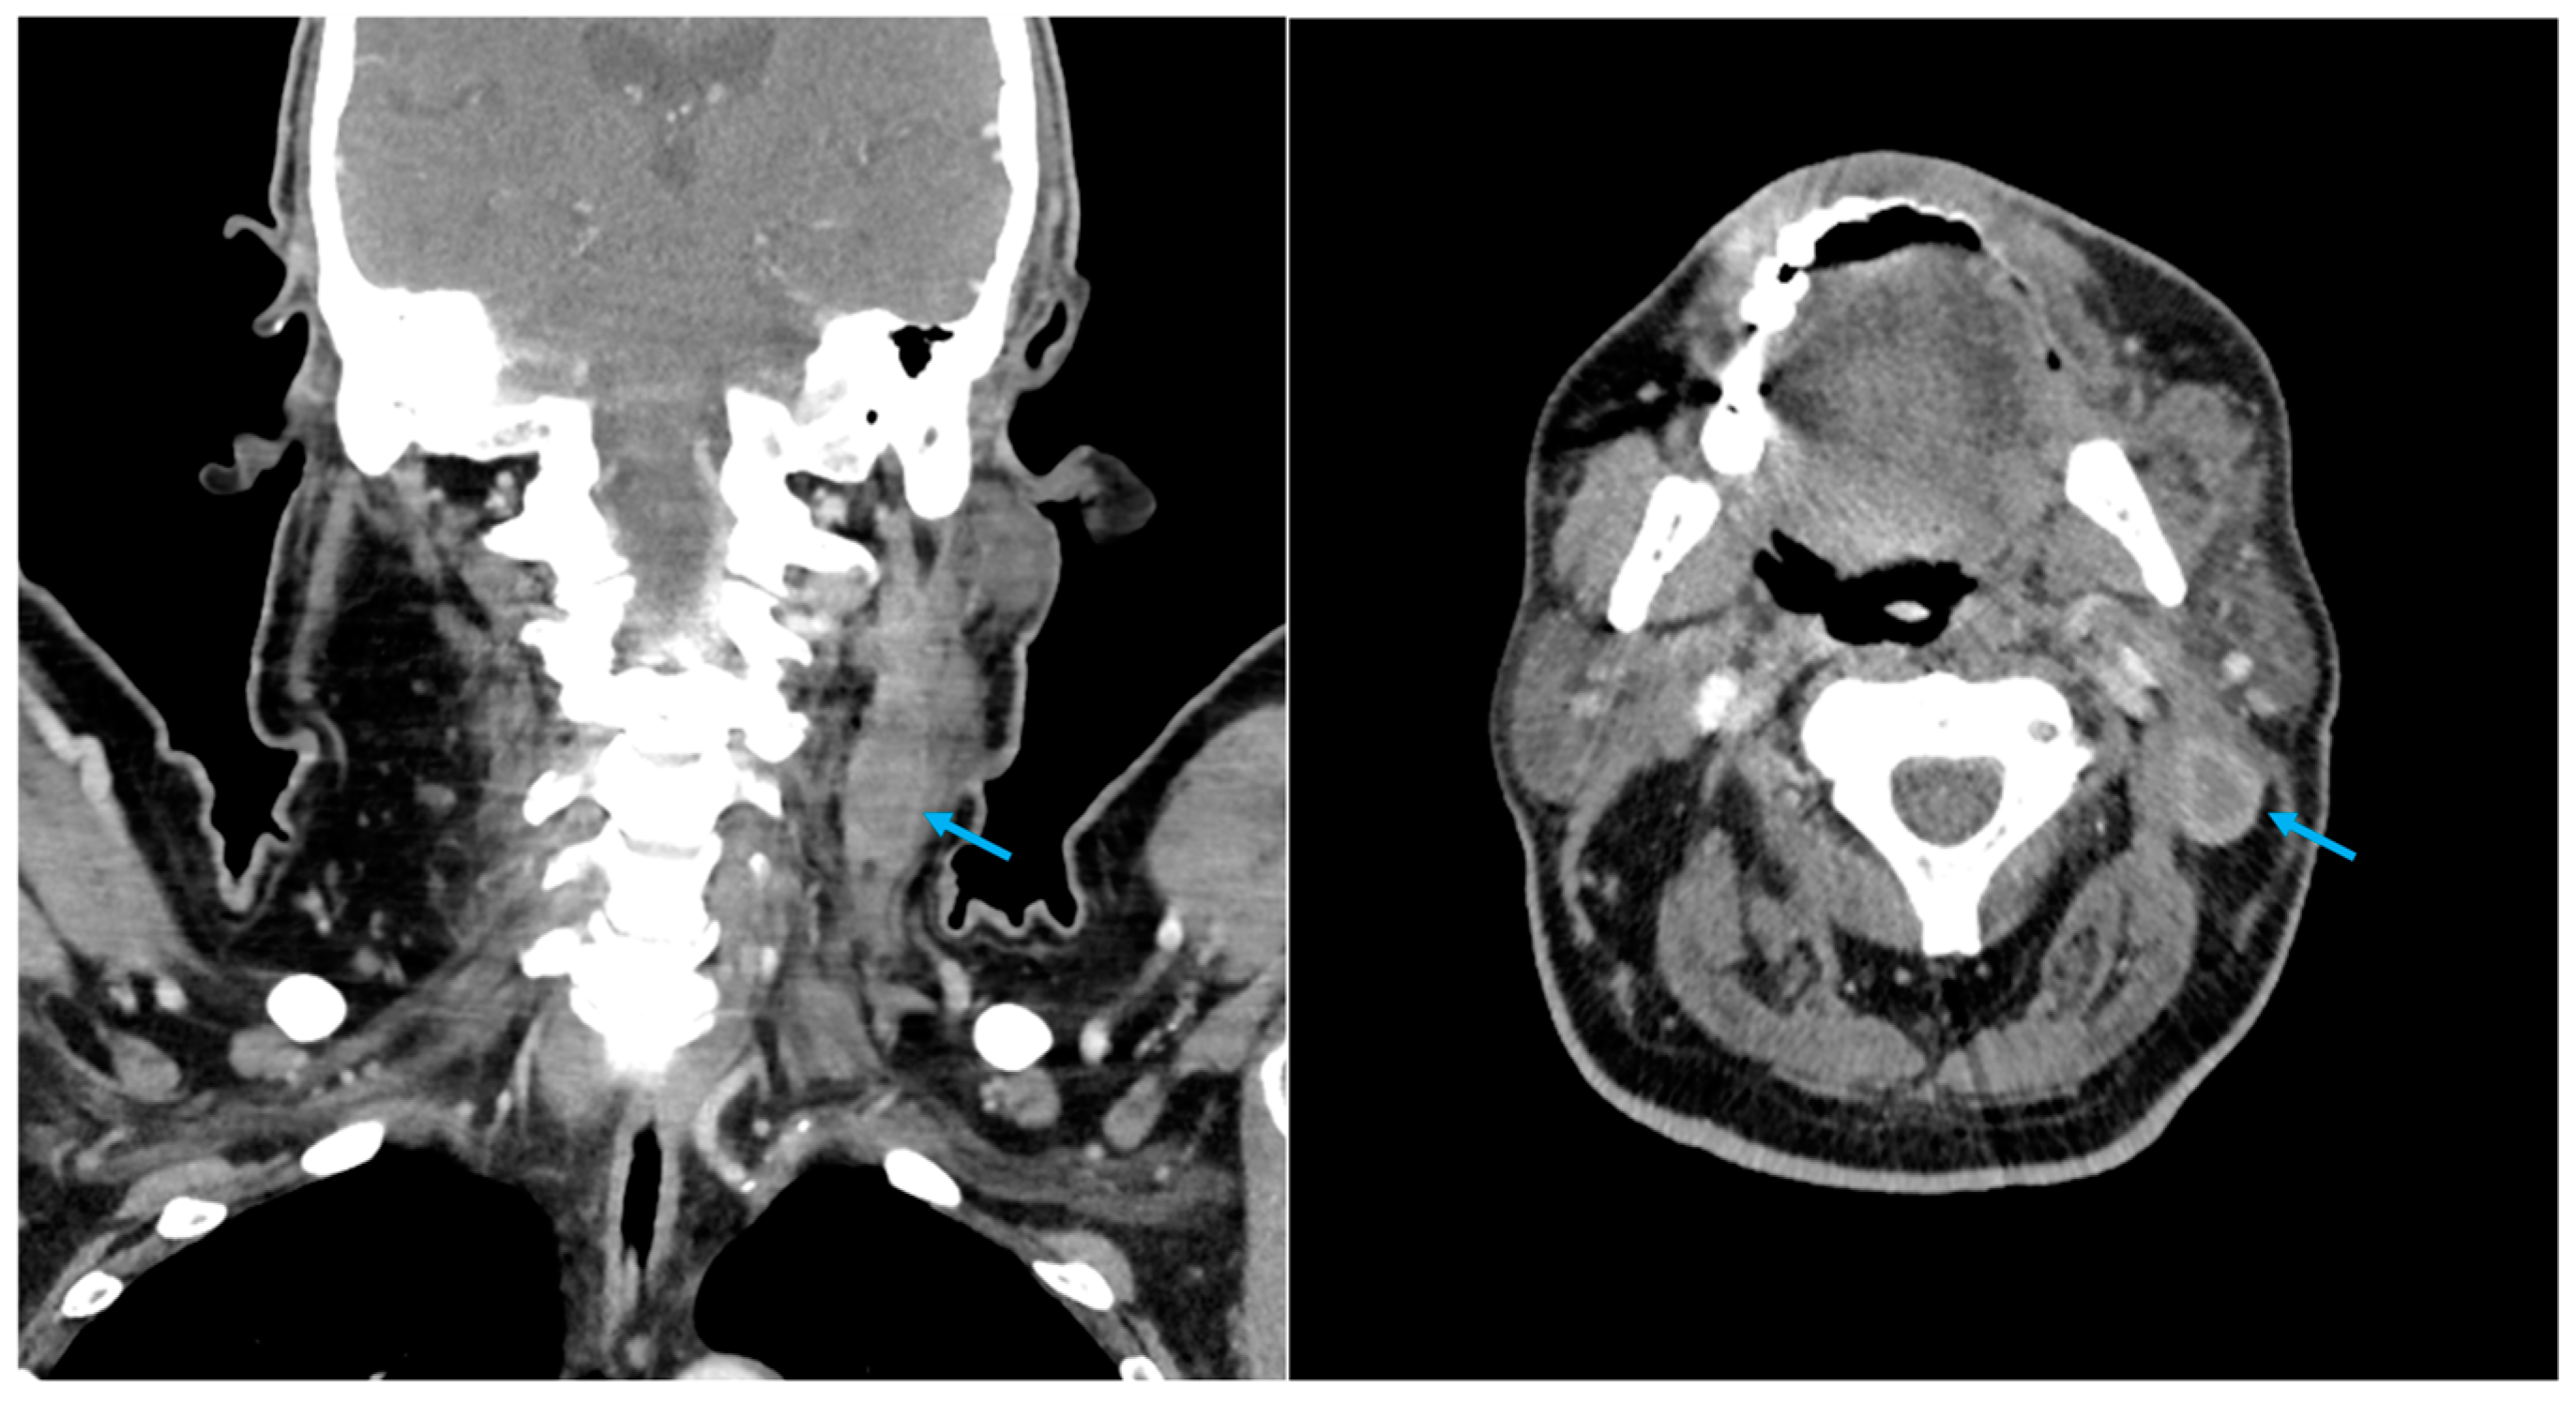

| Presented case 1 | 2024 | Case report | 1 | 78 | F | Maxilla | Tabotamp | Ameloblastoma | Excision of primary tumour | CT + MRI | 15 d | CT + MRI + surgical excison | H |

| Case 1 | Elongated, non-homogenous hyperechogenic formation with an expansive growth pattern | CT (1): Lymphadenopathy […] and exhibited areas of colliquation | Persistent left adenopathy was observed, with no evidence of restricted signal in DWI or post-contrastographic enhancement | Ovoid mass with an elevate 18-FDG uptake (SUV 7, 5) | C (1): Necrotic debris, neutrophilic granulocytes, and rare multinucleated histiocytic giant cells. C (2): Cytological sample revealed the presence of a birefringent material, which was identified as sutures, macrophages, and isolated foreign body-like giant multi-nucleated cells | |